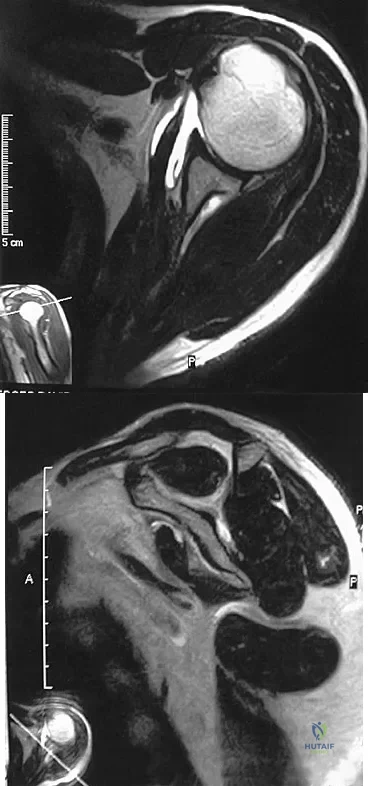

A 54-year man has left shoulder pain and weakness after falling while skiing 4 months ago. Examination reveals full range of motion passively, but he has a positive abdominal compression test and weakness with the lift-off test. External rotation strength with the arm at the side and strength with the arm abducted and internally rotated are normal. MRI scans are shown in Figures 1a and 1b. Treatment should consist of

Detailed Explanation